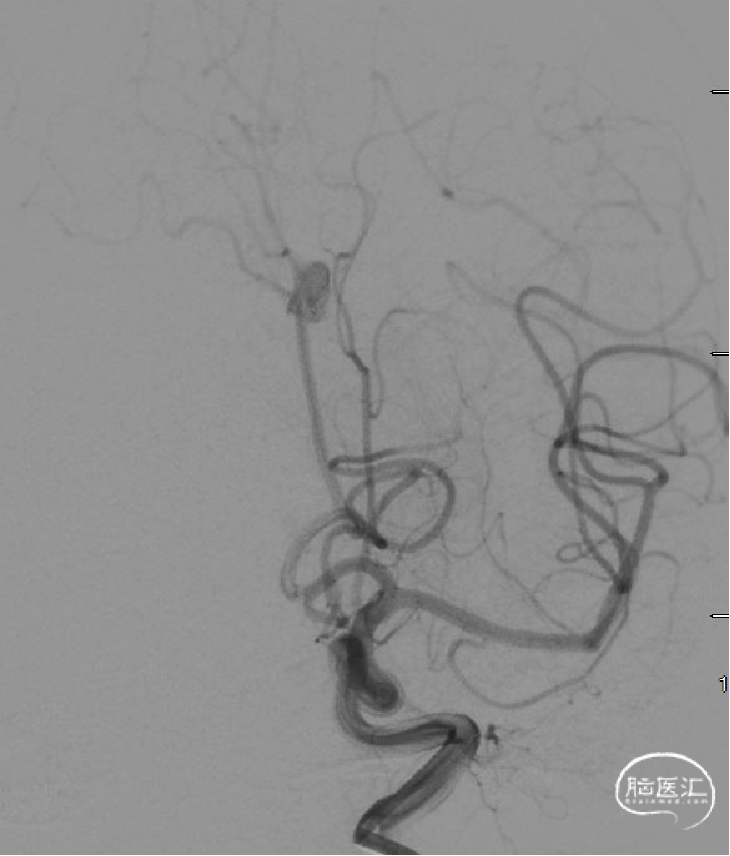

DSA(如下动态影像)。

DSA右侧眼段动脉瘤约4.4mm×4.5mm,左侧A1段动脉瘤约2.7mm×3.0mm。

Atlas释放及术后造影。(如下动态影像)